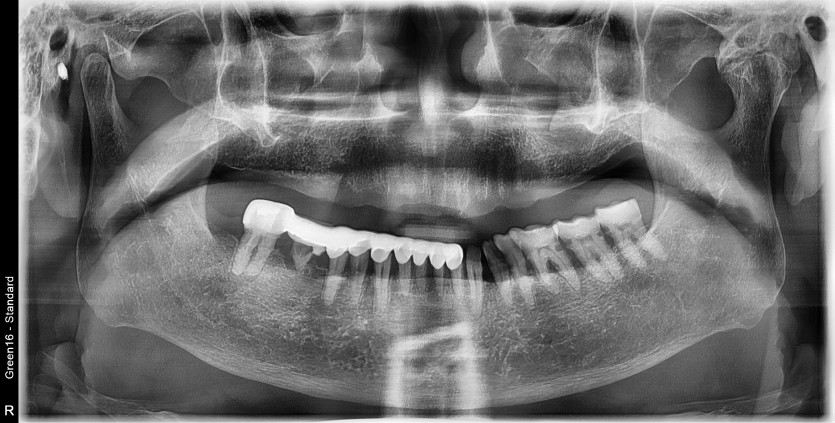

상악 전체 임플란트 증례입니다.

10개의 임플란트로 완성하였습니다.